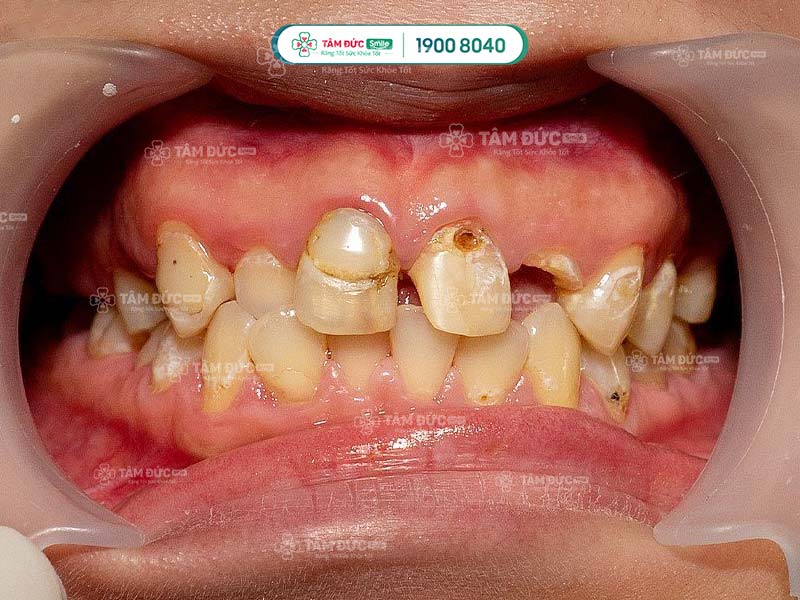

1.1. Sâu răng

Sâu răng là bệnh lý răng miệng phổ biến, có thể dẫn đến mất răng vĩnh viễn. Ở giai đoạn đầu, vết sâu chỉ nhỏ như đầu kim. Nếu Quý khách không chữa trị sâu răng sớm, vết sâu sẽ lan rộng và ăn vào các lớp tổ chức cứng của răng, dẫn đến mẻ vỡ thân răng.